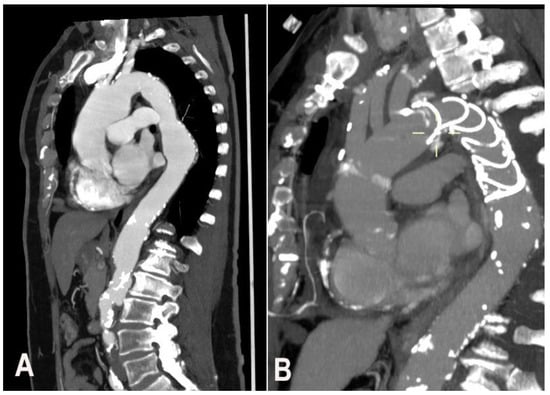

The possibility to use FET depends on entry tear position and involvement of the thoraco-abdominal aorta including visceral branches. The study of visceral branches should be accurately evaluated, because a selective origin from the false lumen represent a contraindication to FET since the high risk of FL thrombosis and hence malperfusion (Figure 1).

Figure 1. (A). Chronic residual aortic dissection, (B) post-operative CT scan, (C) post-operative CT scan reconstruction.